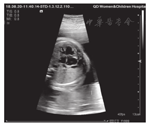

术后密切观察孕妇宫缩及胎心情况,注意有无胎儿心律失常及心包积液。术后临时予250 g/L硫酸镁注射液(40 mL/kg)抑制宫缩治疗1次,予口服头孢克洛(0.25 g,2次/d)预防感染,术后1 d复查胎儿超声心动图显示胎儿房间隔过血增多,原有缺损结合打孔后缺损分流口内径共约2.9 mm,但左心房仍小,房间隔凸向右心房提示左心房高压(图3A、图3B)。术后3 d顺利出院,出院后需密切随访。